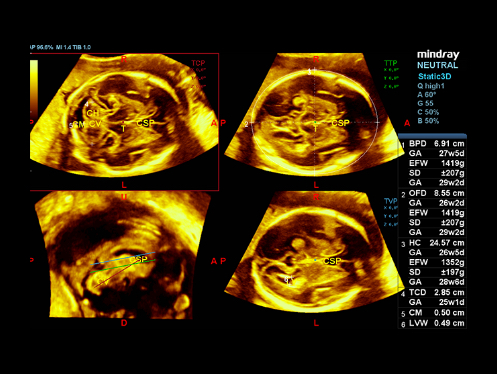

DC-80A con X-Insight mette a disposizione strumenti di una intelligenza eccezionale specifici per la cura della donna, dalla fertilit├Ā allo screening prenatale, e al post partum.

Immagini cliniche